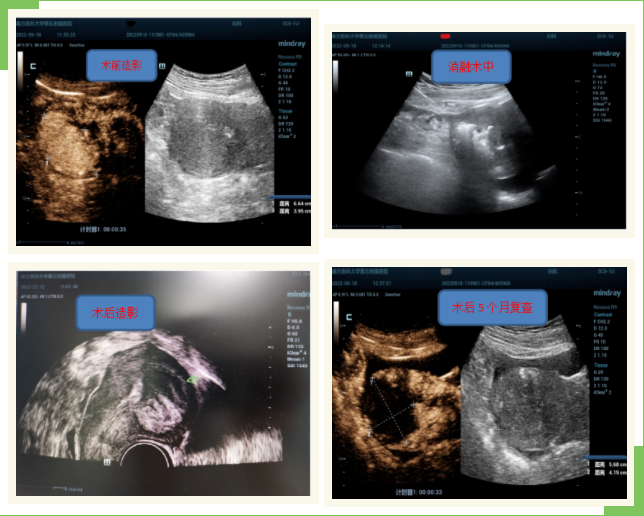

经超声检查,王女士患有明显的子宫腺肌病,子宫增大近球形,主要病变区位于宫底及子宫后壁,经与王女士分析沟通后,其要求进行消融术灭活病灶。于2022年9月18日入院完善术前检查后,邱健民主任的介入超声团队在超声引导下经过近2个小时的消融术顺利将腺肌病灶消融,即时超声造影显示消融区范围57X50X37mm。消融后患者感觉无明显不适,观察2天后出院。术后20天患者已恢复月经,术后精神状态明显好转,一直未出现痛经,月经量也基本正常。2023年2月13日第二次复查彩超,提示消融区范围缩小至37X34X30mm,已较消融前缩小了近50%。已经恢复正常生活和工作的王女士说:“早知道有这样的技术就好了,之前每天都要吃药,不然就严重干扰到工作和生活,太痛苦了。”